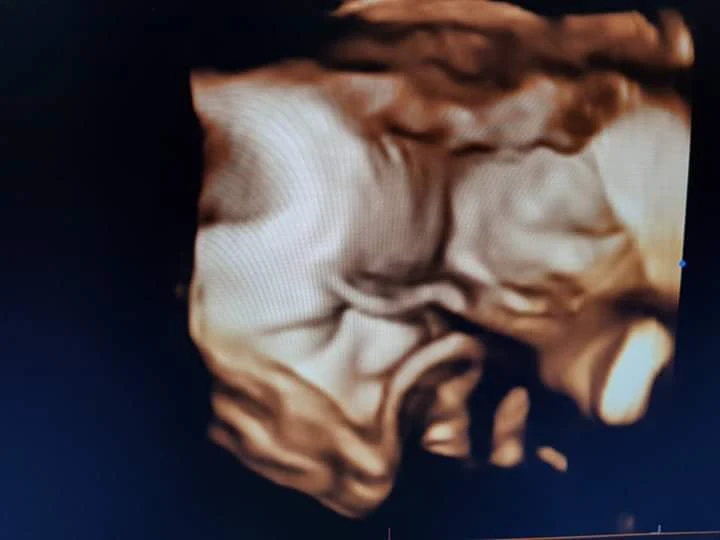

O método de ultra-sonografia 3D (três dimensões) é uma

inovação do método 2D, transforma as imagens convencionais em imagens

tridimensionais, permitindo que a mamãe consiga visualizar uma imagem mais

realista do seu bebê. Essas imagens obtêm uma qualidade quase fotográfica e já

uma realidade na CLIRB.

As melhores imagens da face são obtidas entre 26 a 29 semanas de

gestação, pois neste período o feto já tem uma boa quantidade de tecido

gorduroso em baixo da pele e ainda tem bastante líquido (o que é extremamente

necessário para formação de imagens nítidas).

Veja algumas imagens tiradas por Dr. Geraldo Bensabath